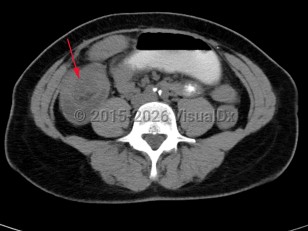

Small bowel obstruction